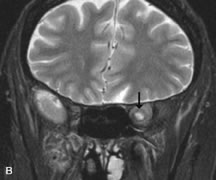

MRI is an excellent modality for demonstrating enlargement of the cavernous sinus and dilation of the superior ophthalmic vein in patients with high-flow carotid-cavernous fistulas (Fig. 14).37MRA may be helpful in the evaluation of the venous outflow pattern. The rapidly flowing blood in these vascular structures carries the excited protons out of the section before they can be imaged, resulting in their dark appearance.5 In low-flow dural arteriovenous malformations, MRA may help define the arterial feeding vessels.45

Fig. 14. Patient with Ehlers-Danlos syndrome who presented with abrupt onset of severe proptosis. A-C. Postcontrast fat-suppressed T1-weighted MR scans demonstrate marked proptosis and engorgement of the extraocular muscles and superior ophthalmic vein (arrows). D. T2-weighted scan through the cavernous sinus demonstrates enlargement and arterialized flow void within the right cavernous sinus (open arrow).